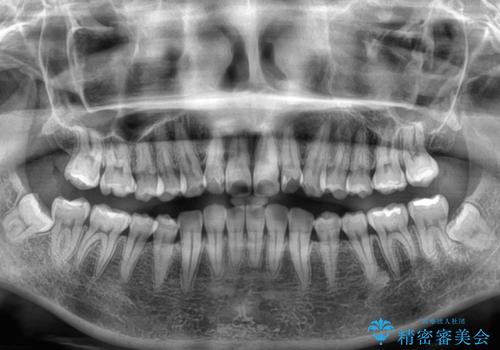

- 前歯のデコボコと突出感を気にして来院された患者様です。

極力目立たない装置を希望とのことで、インビザラインを用いて非抜歯で矯正治療を行うこととしました。

事前に親知らず2本を抜歯し、多少歯列を後方に移動できるように準備をした上で、なるべく歯と歯の間を削ることなくデコボコを解消できるように計画しました。

前歯の捻れを改善するとともに、口元が少しでも引っ込むように治療計画を立て、仕上げることができました。